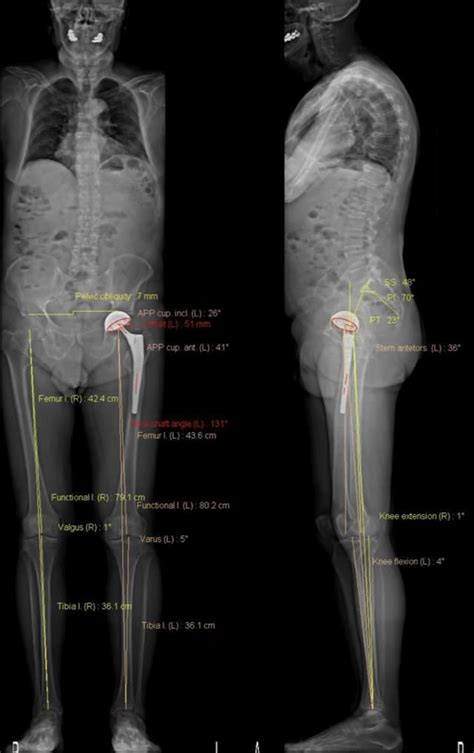

So, what exactly is EOS imaging ? Guys, this is where things get really cool. EOS imaging is a revolutionary medical imaging technology that provides a full-body, 2D or 3D view of a patient’s skeletal structure. Unlike conventional X-rays that take a single snapshot from one angle, EOS captures images from two perpendicular views simultaneously. This unique approach drastically reduces radiation exposure, often by as much as 50% compared to standard X-rays, which is a massive win for patient safety, especially for those who might need multiple scans over time, like growing children or patients undergoing long-term treatment. The system uses a sliding X-ray source and two linear detectors that move around the patient, capturing their entire body from head to toe in just a few seconds. What this means for you is a faster, safer, and more comprehensive scan. The images produced are incredibly detailed, allowing radiologists and orthopedic specialists to get a crystal-clear view of bones, joints, and the spine. This level of detail is crucial for accurate diagnosis, precise surgical planning, and effective monitoring of conditions. Think about it – being able to see the entire skeletal system in a single, low-dose scan? It’s a game-changer! This advanced technology is particularly beneficial in orthopedics, where precise measurements and alignment are paramount. EOS Scan Melbourne brings this state-of-the-art technology to you, ensuring you receive the most advanced care available. It’s all about providing clinicians with the best possible information to make informed decisions about your health. The system’s ability to create 3D models from these low-dose scans is also a huge plus, offering unparalleled insights into patient anatomy that were previously impossible or required much higher radiation doses. We’re talking about understanding the full picture of your skeletal health like never before, right here in Melbourne.

Okay, so why should you specifically look for EOS Scan Melbourne when you need imaging? Great question! Firstly, it’s all about access to cutting-edge technology . Melbourne is a city that prides itself on innovation, and when it comes to healthcare, this means you can find facilities equipped with the latest advancements. EOS imaging is at the forefront of diagnostic imaging, offering benefits that traditional methods just can’t match. The reduced radiation dose is a major selling point. For patients, especially children and adolescents who are still growing or those who require frequent monitoring for conditions like scoliosis, minimizing radiation exposure is incredibly important. EOS scans significantly lower this risk, making it a much safer option for repeated imaging. Think about the peace of mind that comes with knowing you’re undergoing a procedure that prioritizes your long-term health. Secondly, the image quality and comprehensiveness are unparalleled. EOS provides full-body images in a single scan, capturing both frontal and lateral views simultaneously. This allows for a complete assessment of your skeletal structure, from head to toe. Orthopedic surgeons, for example, can use these detailed scans to plan complex surgeries with much greater accuracy. They can visualize the entire musculoskeletal system in 3D, identify potential issues, and determine the best course of action before even stepping into the operating room. This translates to potentially shorter surgery times, improved outcomes, and faster recovery for patients. EOS Scan Melbourne ensures you get this superior diagnostic information. Furthermore, the speed and efficiency of the EOS system are significant advantages. The scan itself is very quick, taking only a few seconds to capture the necessary images. This not only makes the experience more comfortable for the patient but also increases throughput for the facility, meaning less waiting time for appointments. In a bustling city like Melbourne, efficiency matters! Finally, it’s about better patient outcomes . By providing clinicians with more accurate, detailed, and comprehensive information, EOS imaging leads to more precise diagnoses, better-tailored treatment plans, and more effective monitoring. This ultimately contributes to improved patient care and overall health results. So, when you’re looking for imaging services in Melbourne, choosing a facility that offers EOS Scan Melbourne means opting for safety, accuracy, efficiency, and the best possible chance for a positive health outcome. It’s an investment in your well-being, leveraging the most advanced tools available.

Guys, the versatility of EOS imaging means it’s making a huge impact across various medical specialities, and EOS Scan Melbourne facilities are leveraging this technology for a range of applications. One of the most significant areas is orthopedics , particularly in the diagnosis and management of spinal conditions like scoliosis. Traditional scoliosis screening often involves multiple X-rays taken at different times and angles, accumulating a considerable radiation dose. EOS, however, can capture a simultaneous, full-spine frontal and lateral view with a significantly lower dose. This allows orthopedic specialists to precisely measure spinal curvature, assess rotation, and track progression over time with incredible accuracy, which is vital for determining the best treatment, whether it’s bracing or surgery. Think about how much easier it is for doctors to plan corrective surgery when they have a complete, low-dose 3D model of the spine! Beyond scoliosis, EOS imaging is invaluable for assessing other orthopedic issues, such as hip dysplasia, limb length discrepancies, and joint alignment problems. Surgeons can use the detailed 3D reconstructions to plan hip replacements, knee surgeries, or corrective osteotomies with a level of precision that was previously unattainable. This means better implant positioning, more balanced results, and ultimately, improved function for the patient. Another key application is in pediatric orthopedics . Children’s developing bodies require careful monitoring, and the low radiation dose of EOS is a huge advantage. It allows for frequent assessments of conditions like hip problems or limb deformities without unduly exposing young patients to unnecessary radiation. EOS Scan Melbourne is thus a crucial tool for ensuring the healthy development of our younger population. The technology also finds applications in rheumatology for assessing joint damage and monitoring the progression of diseases like arthritis, and even in oncology for evaluating bone tumors and planning treatment. The ability to generate accurate 3D models is also a boon for rehabilitation and physical therapy , allowing therapists to understand a patient’s biomechanics more thoroughly and design personalized exercise programs. Essentially, wherever precise skeletal assessment is needed, EOS Scan Melbourne offers a superior solution, combining diagnostic power with patient safety. It’s transforming how we approach musculoskeletal health, making diagnostics more informative and treatments more effective.